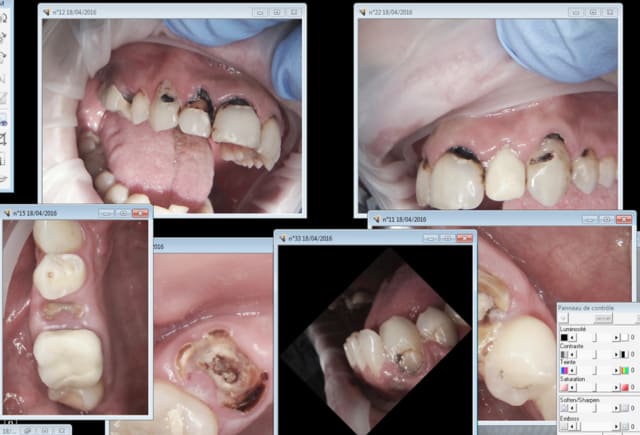

Quand tu en as un qui arrive dans cet état tu fais comment ? Tu le soignes avec un "acte de soin sera payé, au minimum du minimum, pour faire semblant." Ou tu fais semblant de le soigner ? -))

Capture d e cran 2016 04 18 12.33 - Eugenol

Capture d e cran 2016 04 18 12.34 - Eugenol